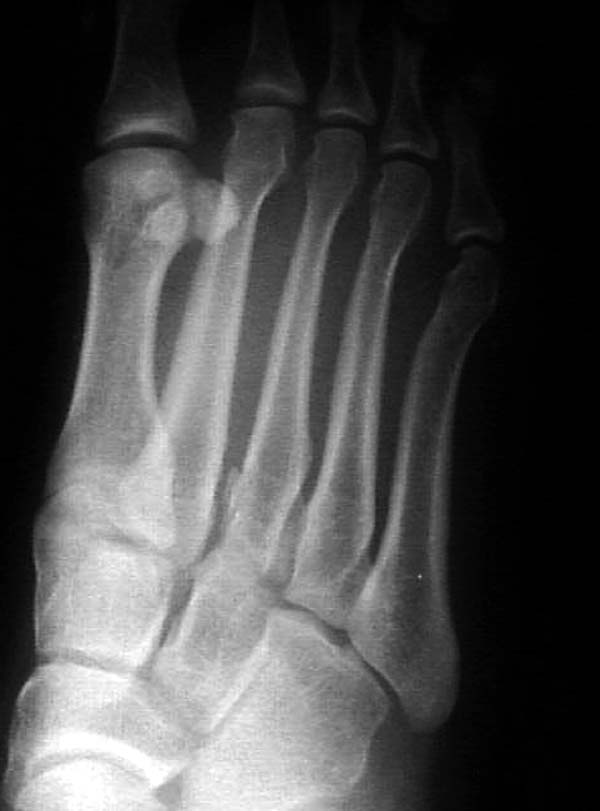

По снимкам нельзя исключить разрыв связки Лисфранка (связки между медиальной клиновидной костью и основанием второй плюсневой). Помогает в диагностике клиника (наличие изолированной гематомы на подошвенной поверхности стопы) и МРТ картина. Если связка повреждена - необходимо оперативное лечение.

По первому снимку, не видя больного, мог бы заподозрить перелом основания 3-й плюсневой кости. Поэтому избрал бы тактику консервативного лечения, как при переломе плюсневых костей без смещения!